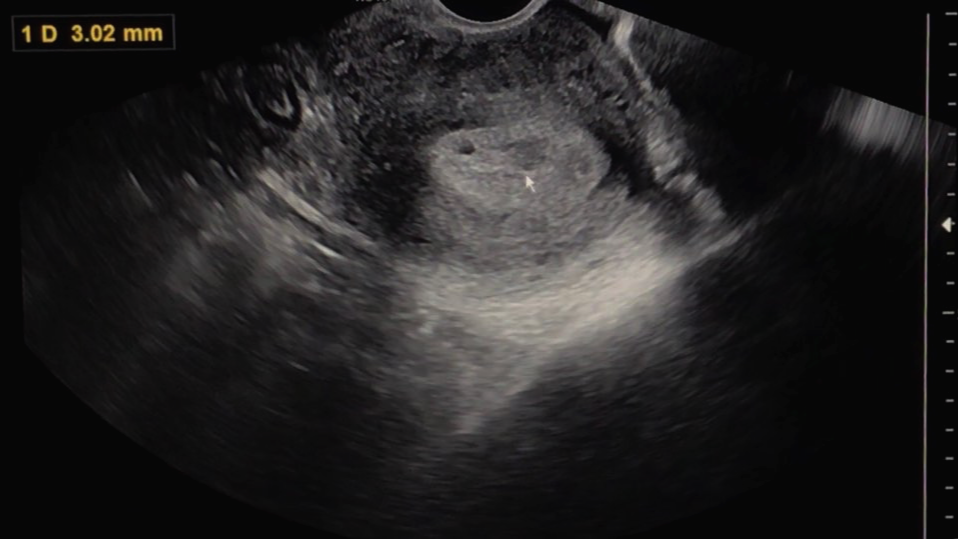

그리고 선생님은 초음파를 보면서 어떤 상태인지 한번 자세히 보자고 말씀하셨습니다.

아직은 확실하게 '아기집이 이거다!' 하고 보이지는 않는 상태이지만 와이프의 몸 안에 무언가가 생기기는 했나 봅니다.

확실히 아기집이 생겼다고 말씀을 안 해주시는 걸 보면 원장님 또한 아직은 조심스러운 상태이신 게 맞는 것 같습니다.